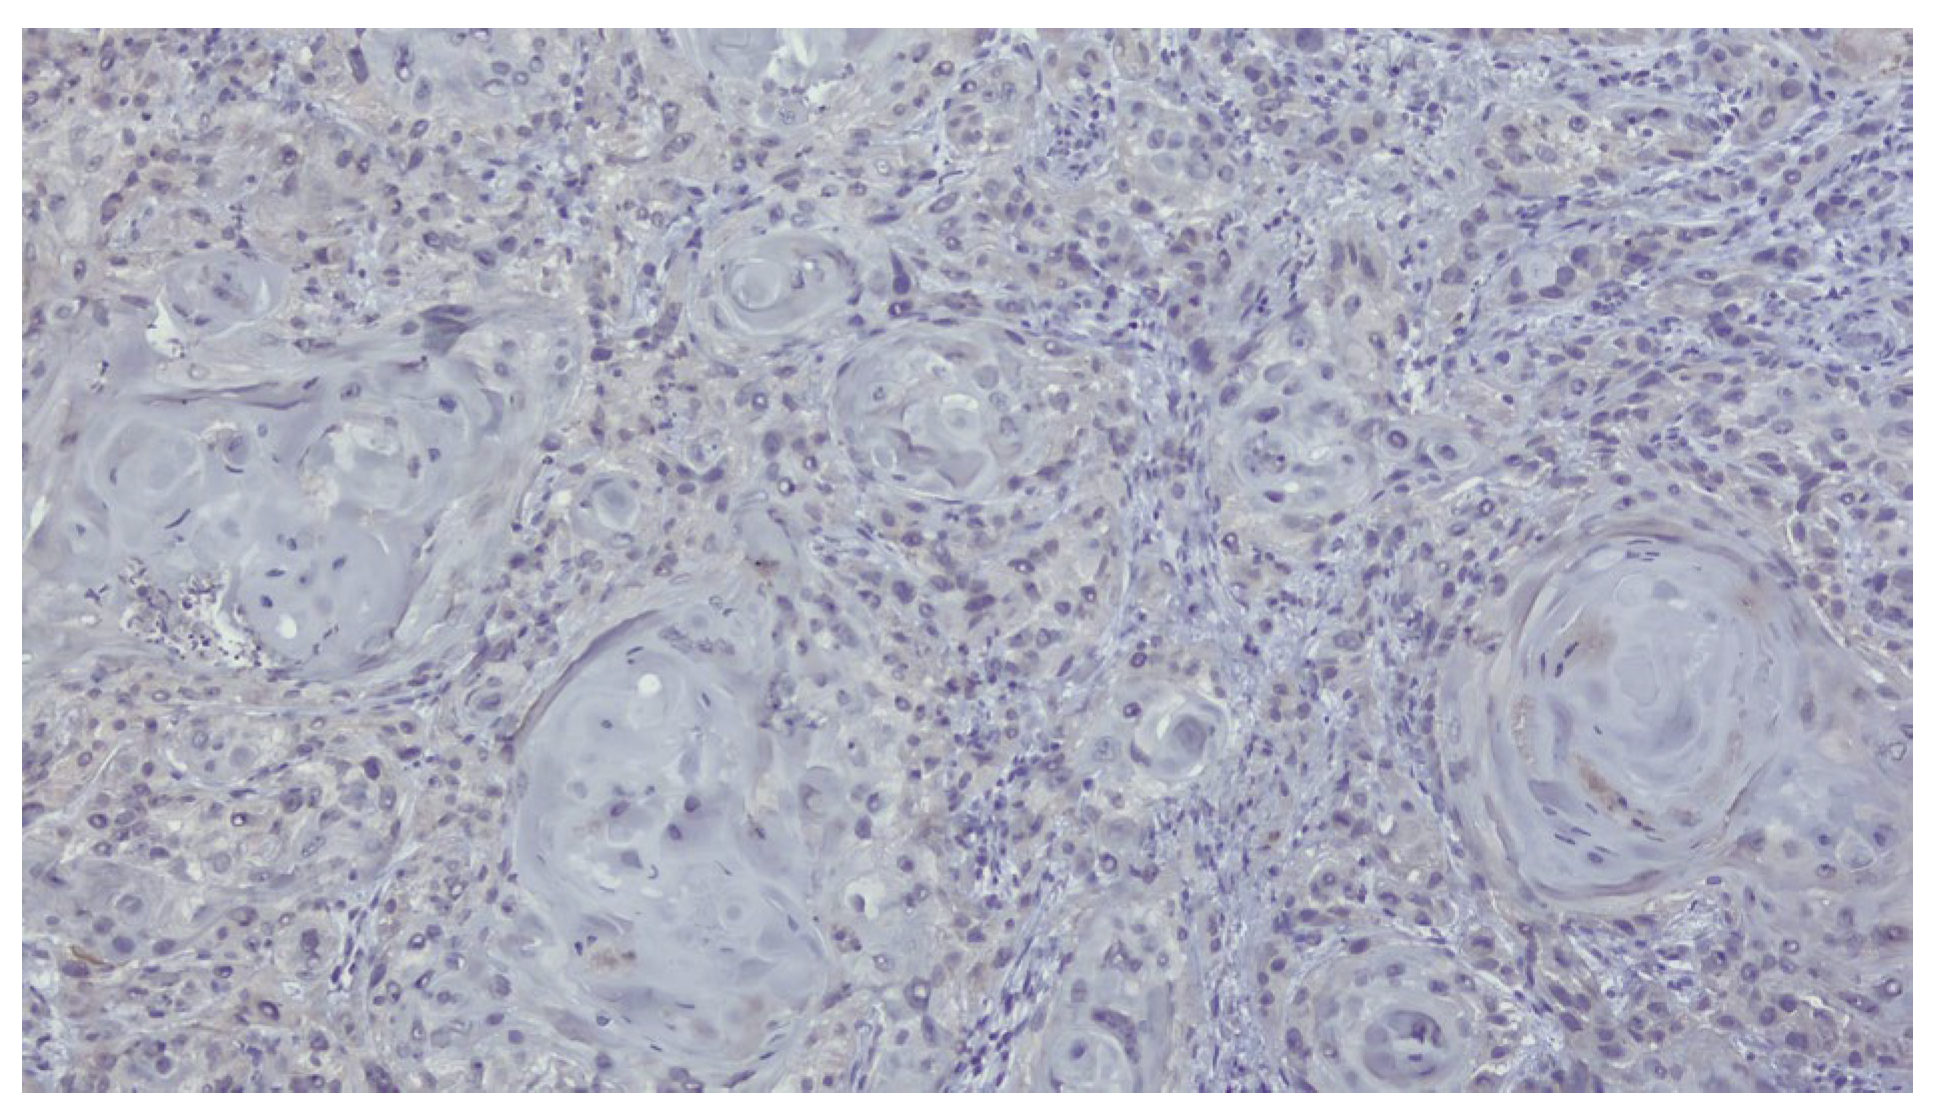

The patient was referred to the Department of Oral and Maxillofacial Surgery for further evaluation and management. Following an outpatient consultation and comprehensive clinical examination, no palpable cervical lymphadenopathy was identified on physical assessment. Incisional biopsy of the oral lesion was performed under local anesthesia and the histopathological analysis of the biopsy specimen subsequently confirmed the diagnosis of moderately differentiated keratinizing squamous cell carcinoma grade II Immunohistochemical staining for p16 was also performed and showed a negative result, indicating that the lesion was not HPV-related but more consistent with a conventional, tobacco-associated carcinogenesis pathway (Figure 2).

Figure 2.

Biopsy-immunohistochemical reaction-p16 marker-negative.